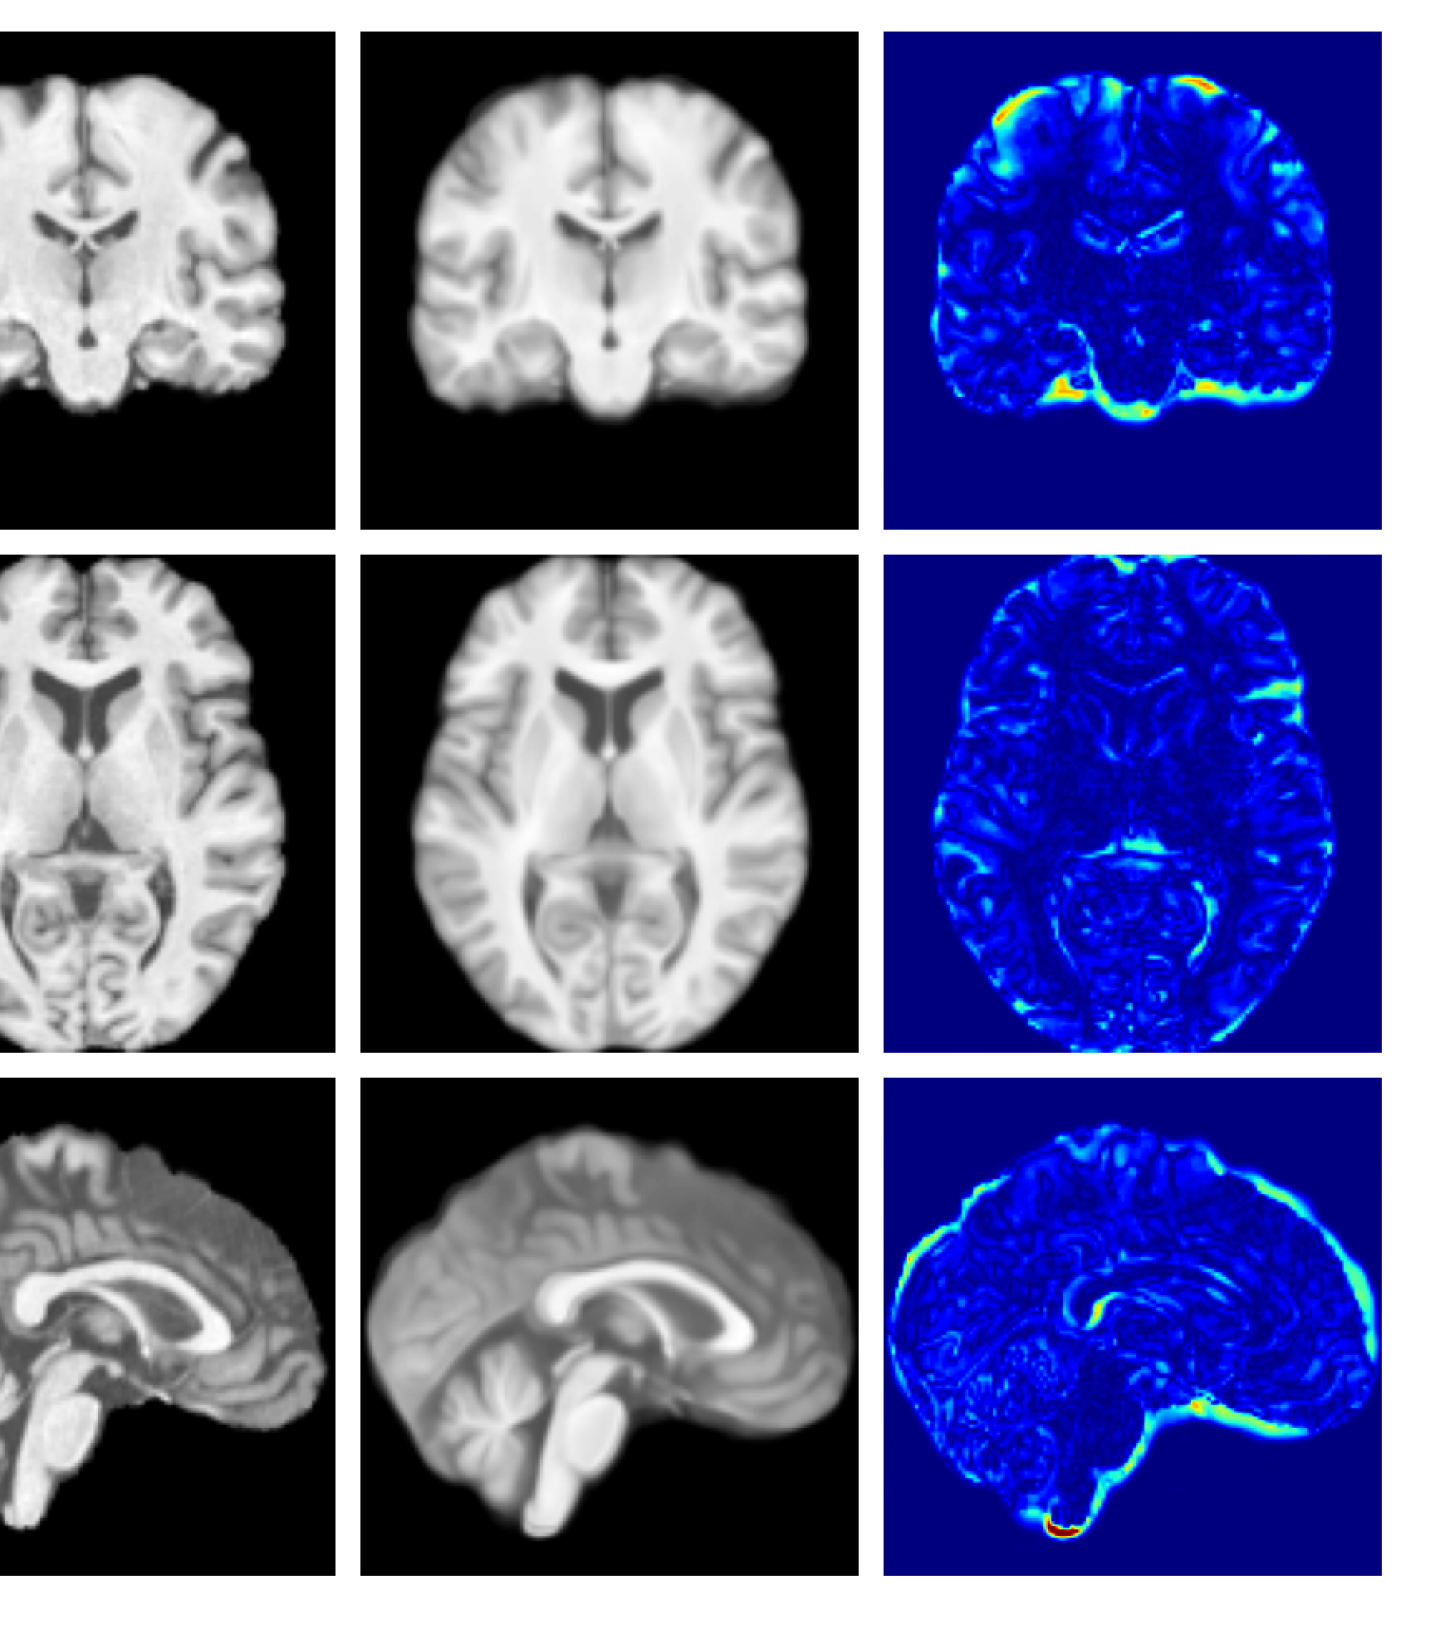

Figure 3: Example reconstructions and anomaly maps for a sample from the disease cohort of the UKBB dataset. Lesion and WMH are indicated in the original image by the red and yellow boxes respectively.

Figures 3 and 4, show example reconstructions and abnormality maps for a sample from the UKBB and UoTH datasets, respectively. Enlarged figures and additional example qualitative results for the ADNI dataset are available in the Supplementary. In Figure 3 we see that whilst all models are able to detect the lesion visible in the sagittal slice, the VAE, cVAE, LDM and LDM (TavgT_{avg}) produce very smooth outputs or lose defining characteristics and thus exhibit more false positives in healthy tissue. THOR and CADD provide the best results, with CADD better detecting white matter hypointensities (WMH). However, neither method fully inpaints all WMH, potentially due to presence of WMH in the healthy training set.

For the UoTH dataset, Table 2 shows that whilst CADD outperforms all other DDPM methods, it is outperformed by the VAE and cVAE models. Unlike the UKBB and ADNI datasets, the UoTH dataset contains noisy images with larger lesions and regions of pathology. Here, the CADD threshold, which limits the number of regions flagged as anomalous at each inpainting step, may be too stringent to fully inpaint extensive anomalies. It should be noted, however, that the improved disease detection performance of the VAE and cVAE models comes at the cost of accurate reconstruction of healthy tissue as illustrated in Table 1 and Figure 4. Such poor quality reconstructions would not be suitable for downstream tasks such as anomaly segmentation or image processing algorithms.